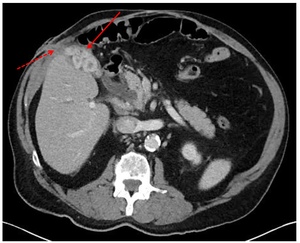

A computed tomography (CT) scan of the abdomen with intravenous contrast showed a gallbladder packed with stones and a CCF extending from the gallbladder fundus through the right abdominal wall. (Figure 2).